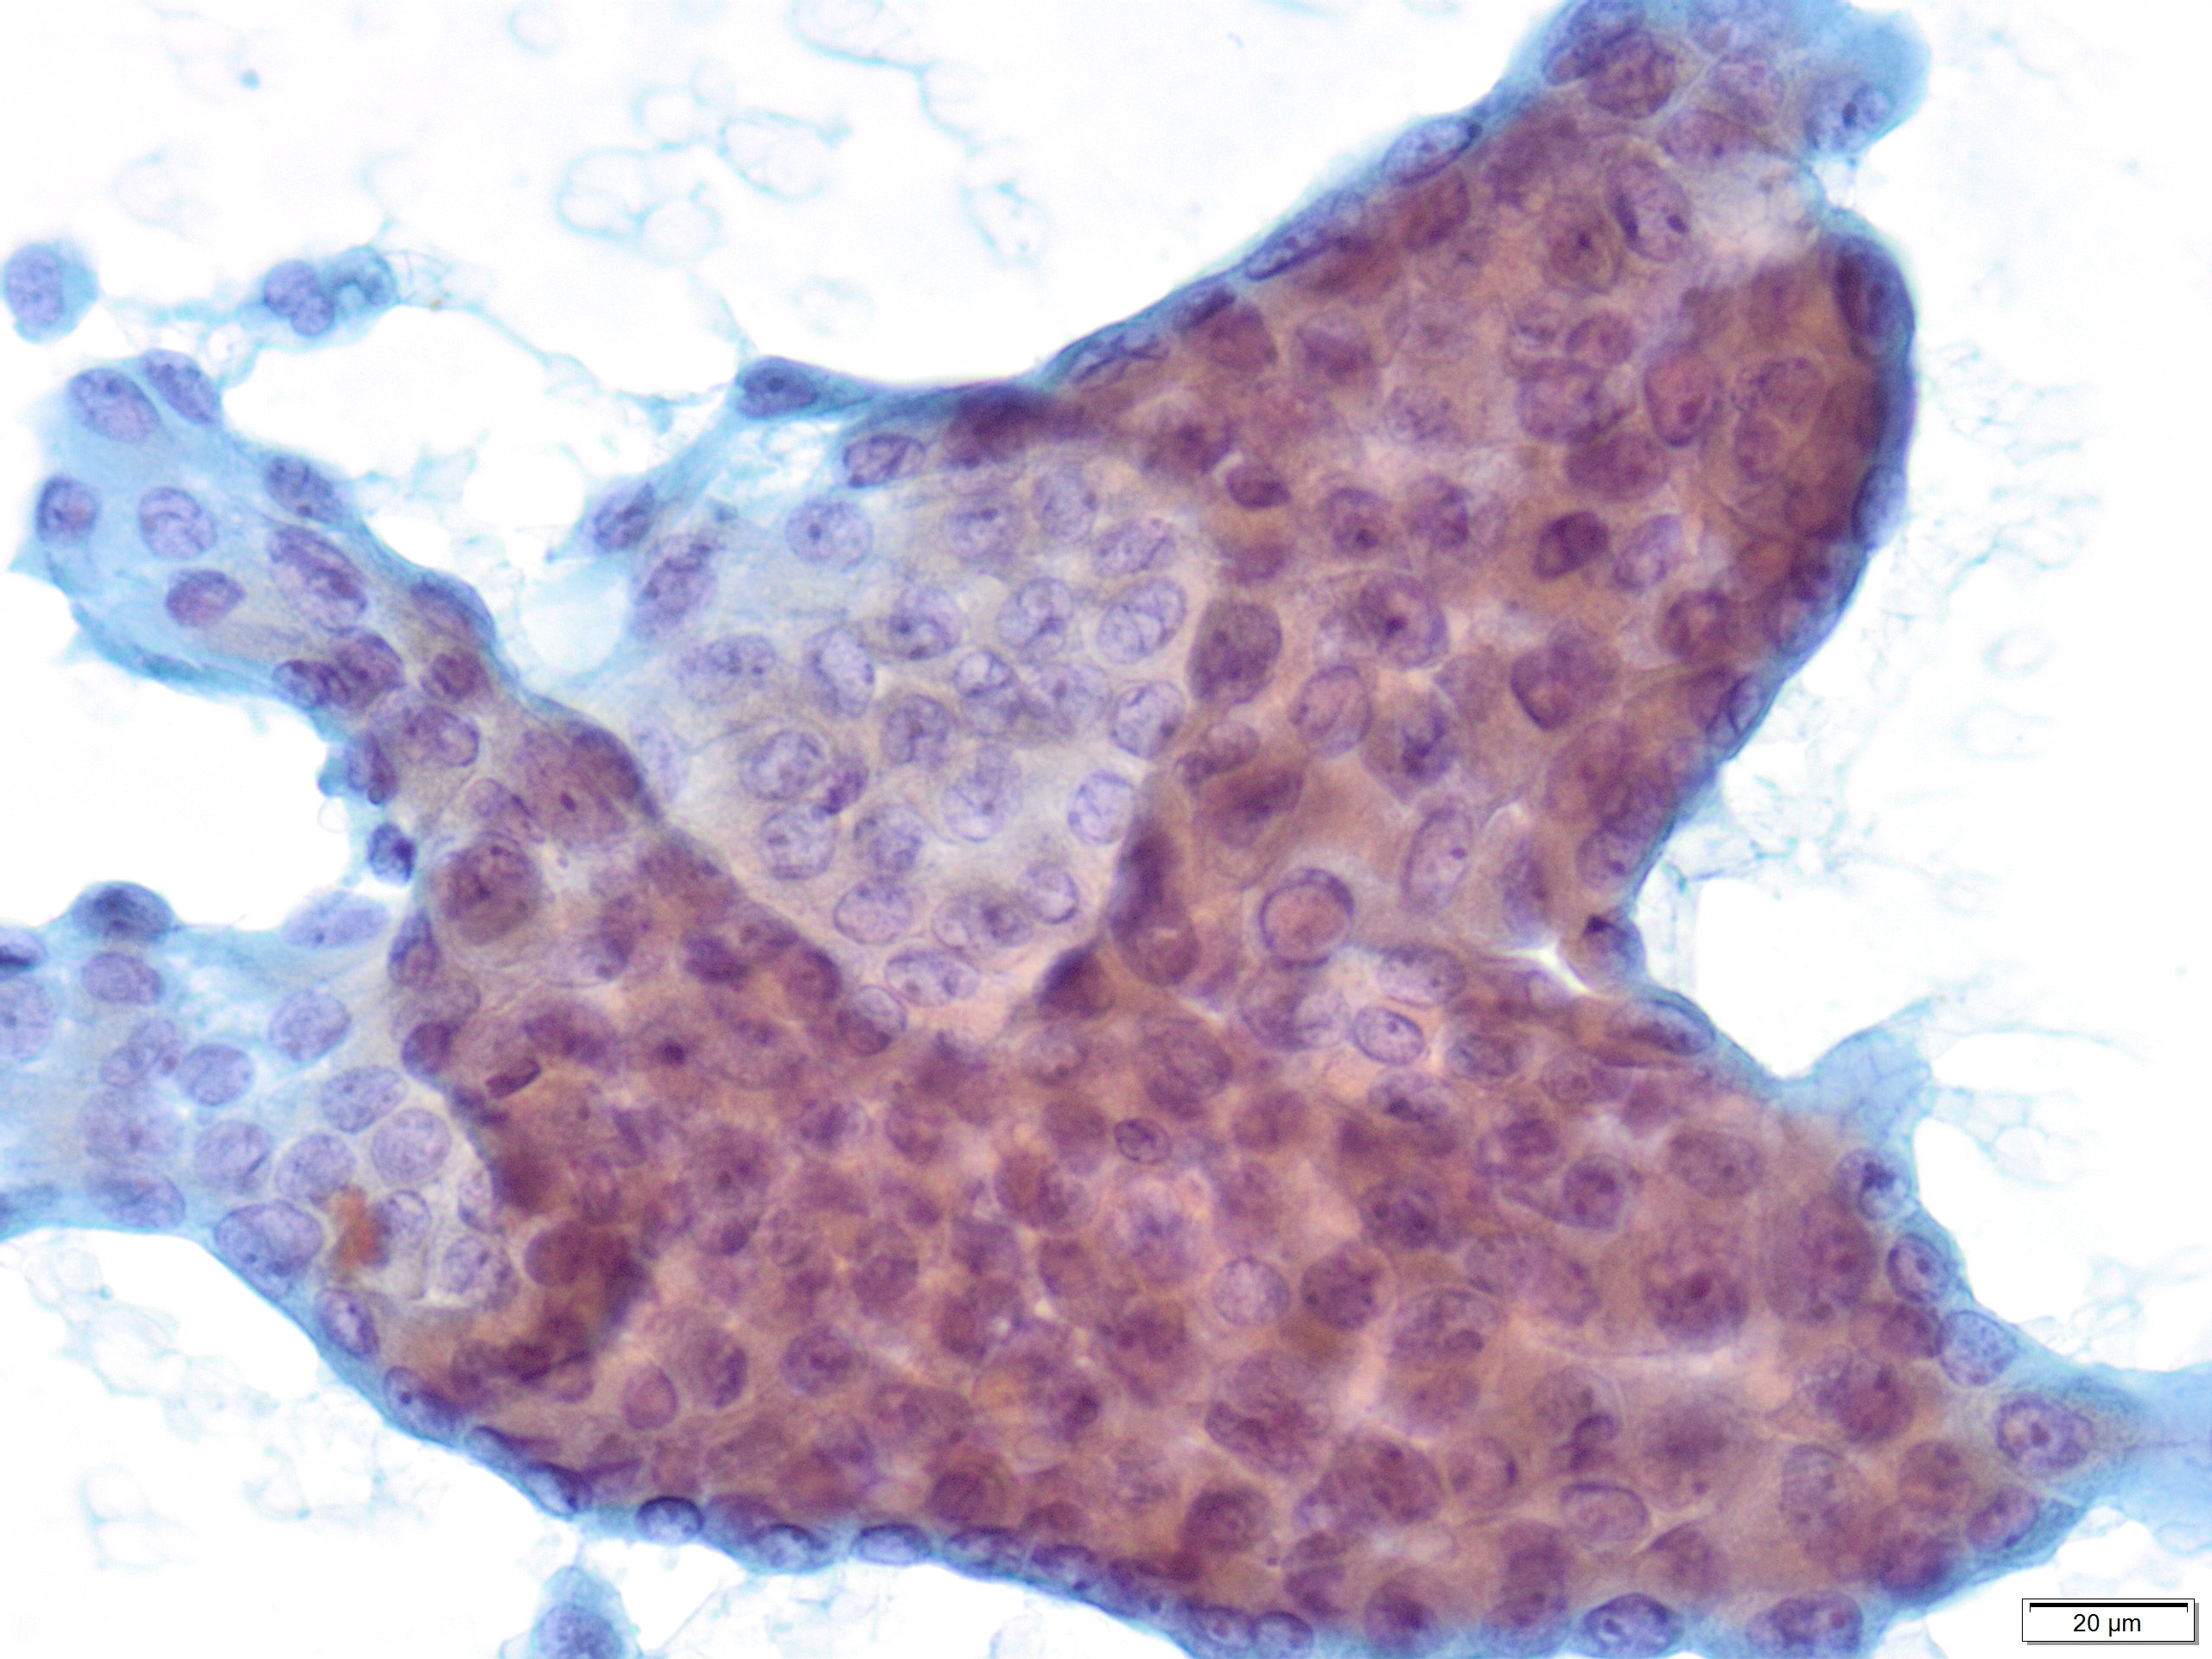

PTC is the most common thyroid malignancy in the United States. It can happen at any age with a female to male ratio of 3:1. The smear are usually cellular with sheets of follicular cells exhibiting nuclear overlapping and/or molding. The cytoplasm can be scant or abundant [squamoid, oncocytic (Picture #2) or vacuolated]. Intranuclear pseudoinclusions (black arrow) are specific to PTC and represent cytoplasmic invaginations. Other non-specific nuclear features include grooves (blue arrow) and nucleoli. Another highly specific feature is the presence of papillae with fibrovascular cores (Picture #3).